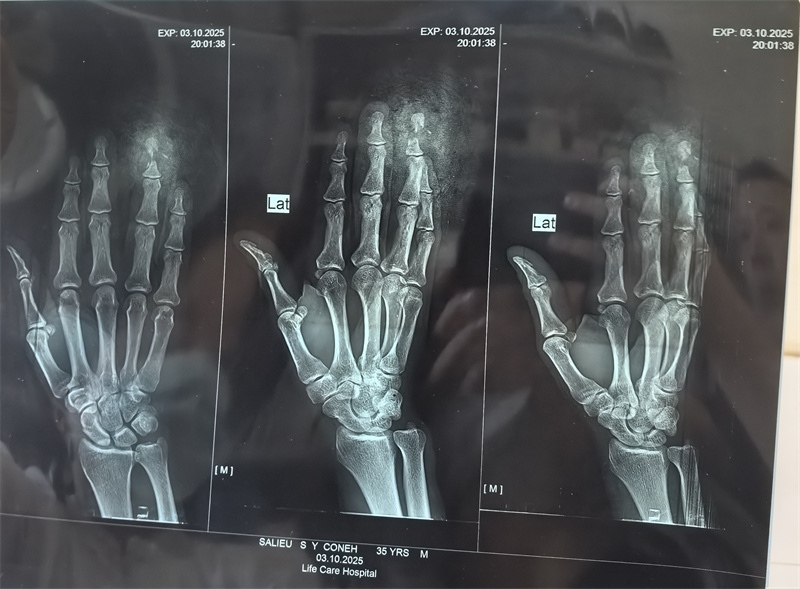

术前X片显示右手环指骨折,软组织损失